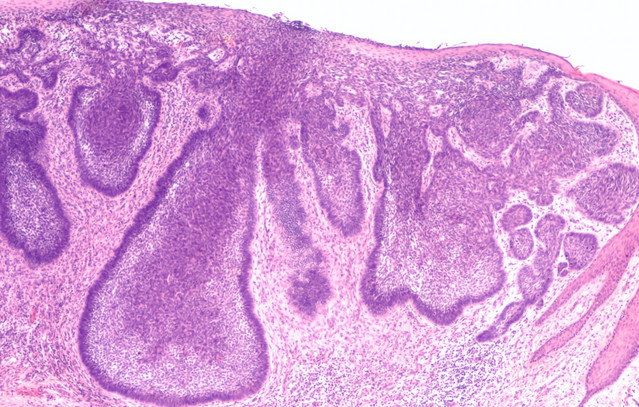

Σχετικά με το πλακώδες καρκίνωμα δέρματος (CSCC)

Το πλακώδες καρκίνωμα δέρματος (CSCC) αποτελεί έναν τύπο μη μελανωματικού καρκίνου του δέρματος (NMSC) και είναι μία από τις συχνότερες μορφές καρκίνου παγκοσμίως. Στην Ευρωπαϊκή Ένωση, η συνολική επίπτωση των μη μελανωματικών καρκίνων του δέρματος (NMSC) αναμένεται να αυξηθεί κατά 40% έως το 2040. Το CSCC μπορεί συχνά να αντιμετωπιστεί επιτυχώς με χειρουργική επέμβαση, ωστόσο πολλοί ασθενείς παρουσιάζουν χαρακτηριστικά υψηλού κινδύνου, καθιστώντας τη νόσο πιο επιθετική και με αυξημένο κίνδυνο υποτροπής και εξέλιξης της νόσου.